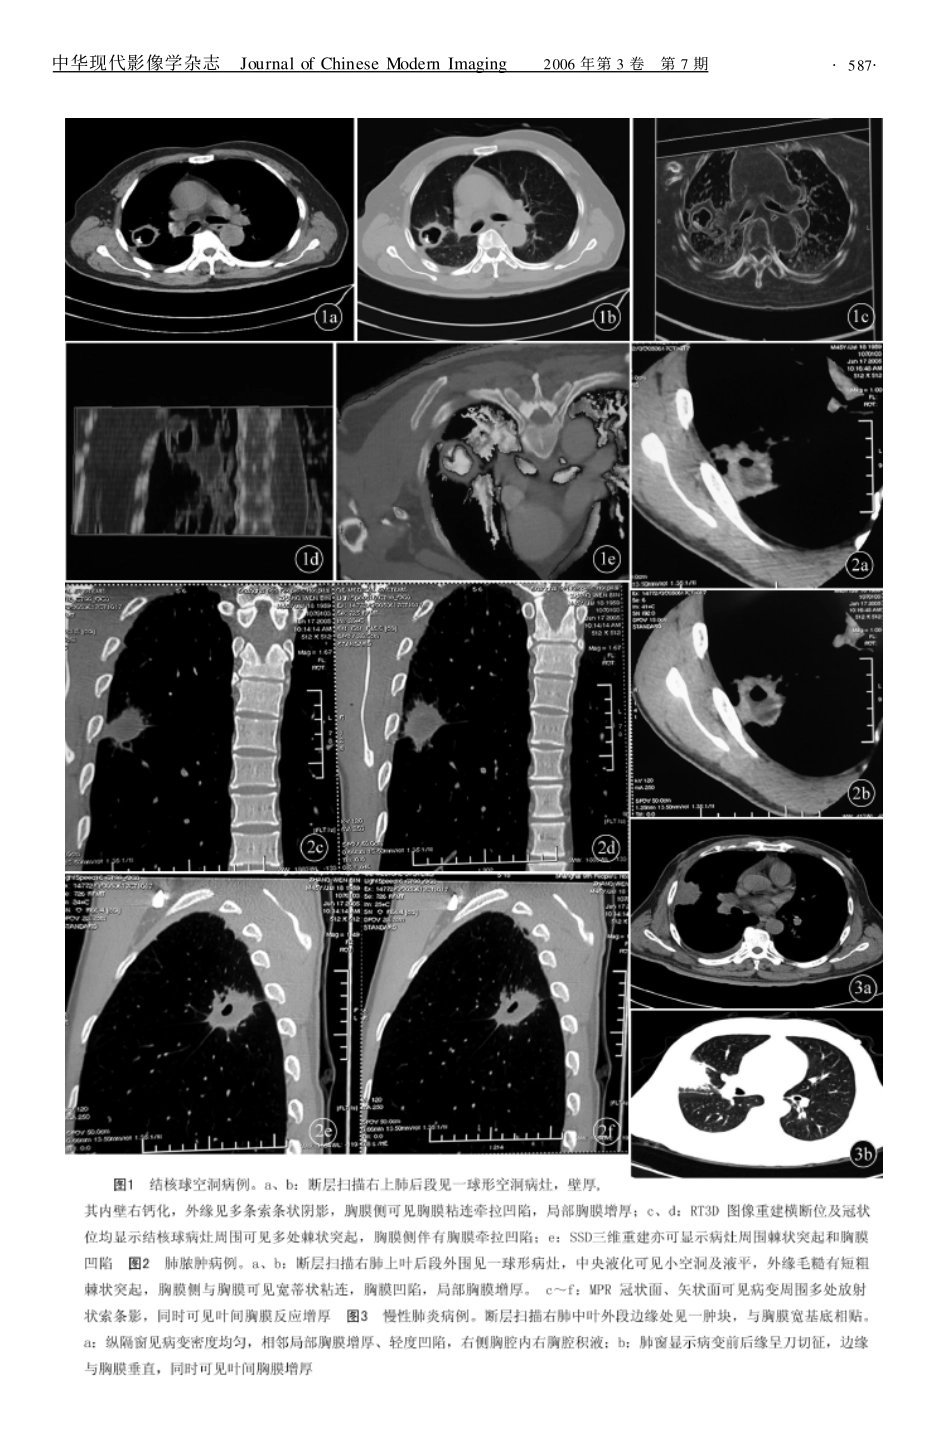

·论著·良性胸膜凹陷的CT诊断张开华,张志勇,唐建华,阎伟伟[摘要]目的研究观察肺内良性病变的胸膜凹陷的CT表现特征。方法收集26例由手术、病理和临床证实并表现有胸膜凹陷征象的肺部良性病变,回顾性分析其CT影像资料。结果肺内良性病变主要是炎性结节9例,慢性炎症6例,结核球5例,炎性假瘤3例,肺脓肿2例,肺曲菌球1例。良性胸膜凹陷的主要CT表现:胸膜棘状粘连牵拉,胸膜宽基底性内凹,相邻胸膜增厚和胸腔积液。结论肺内良性病变所显示的胸膜凹陷具有一定的CT特征表现和临床意义。[关键词]肺;病变;胸膜凹陷;断层摄影术,X线计算机[中图分类号]R814.42;R561[文献标识码]A[文章编号]1681-2824(2006)07-0586-03CTdiagnosisofbenignpleuralindentationZHANGKai-hua,ZHANGZhi-yong,TANGJian-hua,etal.DepartmentofRadiology,TheBranchofZhongshanHospital,FudanUniversity,Shanghai200052,China[Abstract]ObjectiveToinvestigatethecharacteristicCTfindingsofpleuralindentationduetobenignpul-monarylesions.MethodsTwenty-sixcasesofpleuralindentationsduetobenignpulmonarylesionsconfirmedbysurgery,biopsyandclinicwereanalyzedretrospectively.ResultsThemainbenignpulmonarylesionsaccom-paniedwithpleuralindentationwereinflammatorynodule(n=9),chronicpneumonia(n=6),tuberculosis(n=5),inflammatorypseudo-tumor(n=3),abscess(n=2),pulmonaryaspergillosis(n=1).Thecommoncharac-teristicCTfindingsofbenignpleuralindentationincluded:pleuralspeculatedadhesion,pleuralindentationwithwidefoundation,pleuralthickenedandpleuraleffusion.ConclusionThepleuralindentationofbenignpulmo-narylesionhasdistinctiveCTfeatures,whicharehelpfulfordifferentiatediagnosisofpulmonarylesions.[Keywords]lung;lesion;pleuralindentation;tomography,X-raycomputed胸膜凹陷系肺外围占位病变经常伴发的一种影像征象,常规CT扫描时大多数均能明确显示,尤其HRCT和目前采取容积扫描的螺旋CT,结合多种图像后处理方法更能提供准确、详细、有价值的信息。肺部良恶性病变发生胸膜凹陷的病理基础和影像表现各不相同,因此,胸膜凹陷征对肺部实质占位病变的影像诊断是十分重要的。本文收集26例出现胸膜凹陷的肺部良性病变,分析总结如下。1资料与方法1.1一般资料搜集26例经手术、活检病理证实或临床治疗随访证实的肺部良性病变,男17例,女9例;年龄40~72岁,平均56.4岁。所有病例均因常规X线胸片发现肺部病变后,再行CT扫描。临床表现为咳嗽、发热、胸痛和胸部不适23例;体检摄片3例。1.2仪器与方法CT机分别为西门子SOMARTOMEmo-tion、GE公司Lightspeed16螺旋CT全身扫描仪。CT检查均采取胸部常规螺旋扫描,层厚8mm或10mm(其中8mm扫描12例,10mm扫描14例),螺距1.0。一次屏气扫描,扫描范围从肺尖至肋膈角,包括所有肺组织。18例病变区加做靶扫描,层厚2mm或3mm(2mm扫描6例,3mm扫描12例)。全部病例图像均使用纵隔窗(WW:240,WC:60)和肺窗(WW:1700,WL:-600)观察,14例为观察有无叶间作者单位:200052上海,复旦大学附属中山医院分部放射科胸膜或膈面胸膜凹陷等加做图像后处理,如:多平面图像重建(MPR)、实时三维重建(RT3D)、表面遮盖显像(SSD)等。18例做增强扫描,团注法静脉注射对比剂80ml,速率1.8ml/s。2结果26例肺部良性病变均经手术、活检病理或临床证实,包括炎性结节9例,慢性炎症6例,结核瘤5例,炎性假瘤3例,脓肿2例,曲菌球1例。CT表现如下。2.1病灶分布所有实质占位病变或结节均位于肺外围,与胸膜距离0~4cm。其中病变—胸膜间距<1cm12例,1~4cm11例,>4cm3例。病变位于两肺上叶8例,右肺中叶2例,两肺下叶16例。2.2胸膜异常棘状胸膜凹陷16例,肺内病变与胸膜间见粗线状、索条状或棘状高密度影伴胸膜牵拉内陷(图1)。宽基底胸膜凹陷10例,病变胸膜侧>2/3的范围与胸膜粘连相贴,形成盘底征(图2)。胸膜粘连增厚18例。胸腔积液7例。2.3病灶本身变化病变中央密度均匀9例;密度不均17例,其中液化坏死6例,空洞形成5例。边缘光滑见分叶征7例;边缘模糊不清8例,位于病变的远侧;边缘呈刀切样改变6例,表现为病变与胸膜交界面垂直(图...